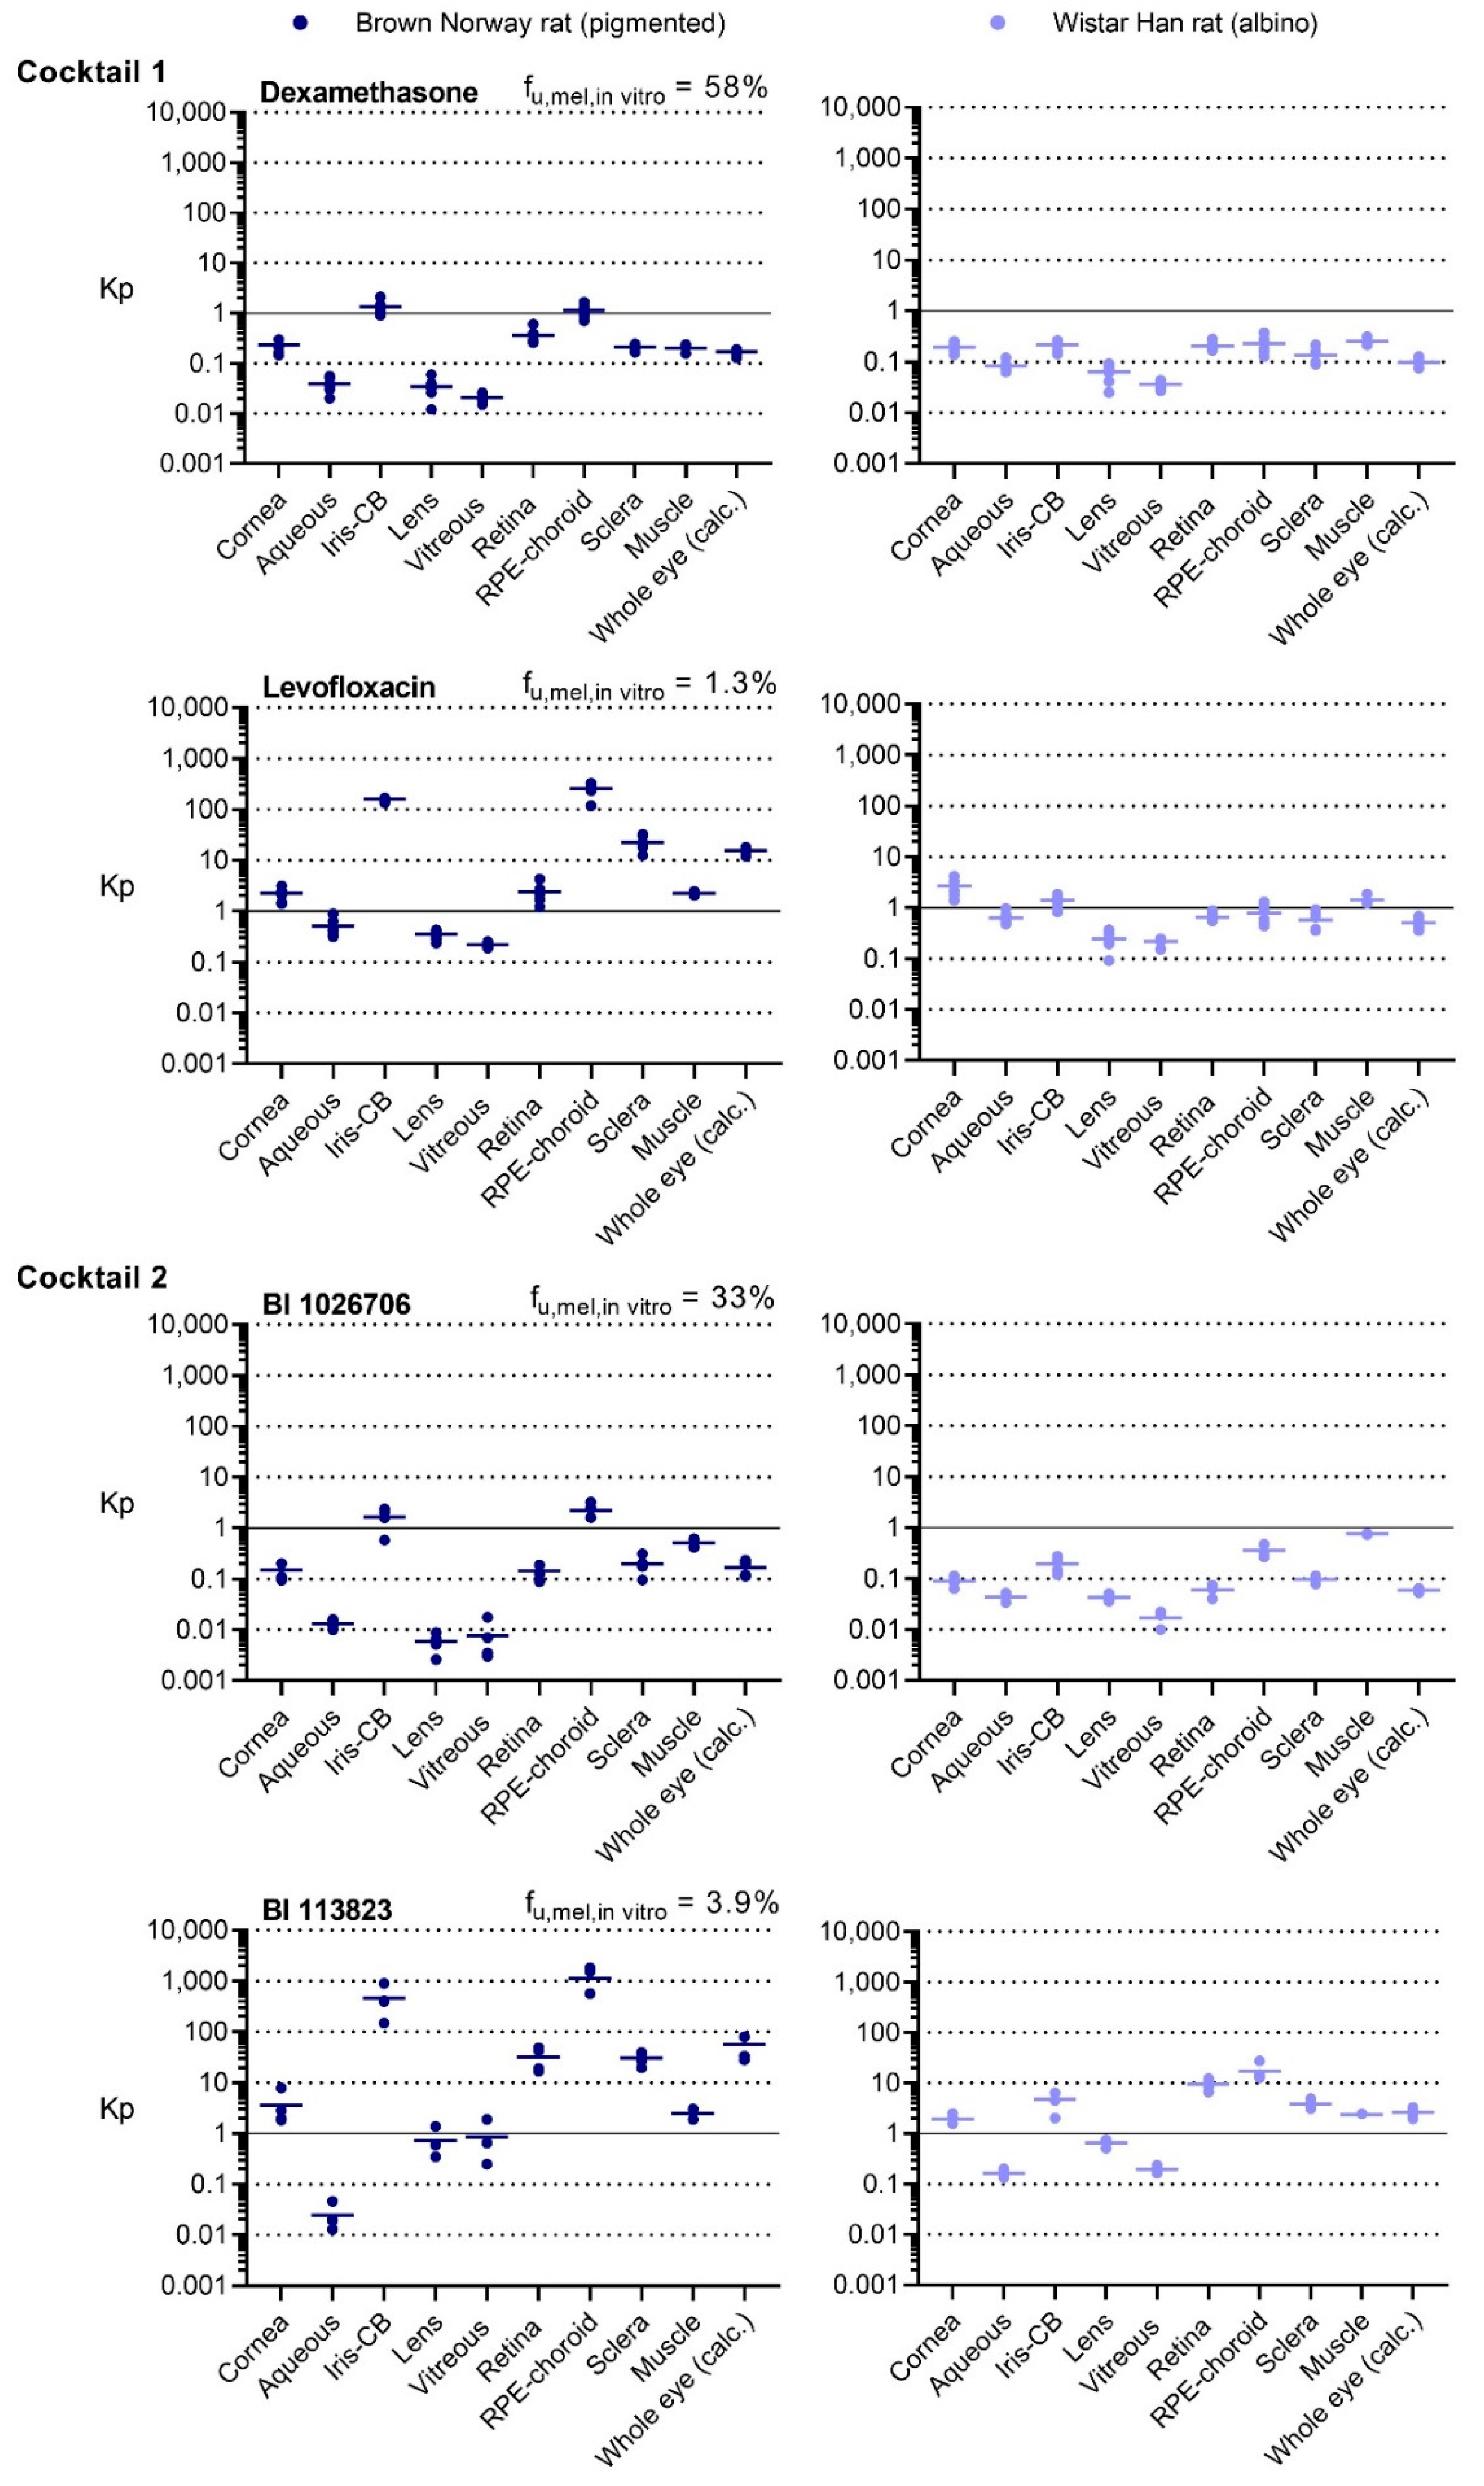

We applied the tissue separation method to determine the ocular concentrations of levofloxacin and dexamethasone, as well as the two proprietary in-house compounds 8 h after oral administration. We could see substantial ocular distribution with BI 113823 and levofloxacin, as most of the ocular tissues had higher concentrations than the concentration in plasma. The two other compounds, BI 1026706 and dexamethasone, had lower ocular distribution with majority of the tissues having lower concentrations than the concentration in plasma. The lower ocular distribution, especially to the non-pigmented tissues, was also linked with a lower distribution to muscle, a well-perfused tissue described generally as a reference for tissue distribution [

17]. The effect of melanin binding on the distribution to the pigmented tissues, RPE-choroid and iris-CB, was extremely evident. The highest differences in Kp between the corresponding BN and WH tissues were observed for the highest in vitro melanin binder levofloxacin in the RPE-choroid (320-fold), whereas the lowest differences (5-fold) were observed for the lowest melanin binder, dexamethasone. The inter-individual variability of the Kp values was low, which demonstrates the reproducibility of the method. Due to the limited concentration data from different tissues of the rat eye available in literature, we cannot thoroughly compare our results to existing data with other tissue isolation methods. However, two ocular distribution studies after oral administration of levofloxacin by Tanaka et al. [

The importance of measuring concentrations directly from the tissue of interest is evident from the observed differences in distribution to individual ocular substructures. Whole-eye exposure, commonly used as a surrogate for ocular tissue distribution, does not correctly describe the exposure in the different substructures (

Figure 3). Larger differences among the individual substructures and between the whole-eye and individual tissue concentrations can understandably be seen in pigmented rats, where melanin binding increases the concentrations in the pigmented tissues. Nevertheless, up to 100-fold differences between substructures were also seen in albino animals: For BI 113823, we found a 16-fold lower concentration in the aqueous humor and a 6.5-fold higher concentration in the RPE-choroid compared to the whole eye, demonstrating the difficulty of estimating individual tissue concentrations from the whole-eye concentration. Moreover, extrapolating from one ocular tissue to another, for example from the vitreous to the other tissues of the posterior segment, can be misleading. Retina/vitreous ratios varied from 3.5- to 48-fold in the WH rat and from 11- to 37-fold in the BN rat. The RPE-choroid/vitreous ratios varied from 3.7- to 87-fold and from 55- to 1,300-fold in the WH, and BN rats, respectively.

In addition to the expected and already described concentration differences in RPE-choroid and iris-CB of WH and BN rats, there were also clear inter-strain differences in partitioning to other tissues (